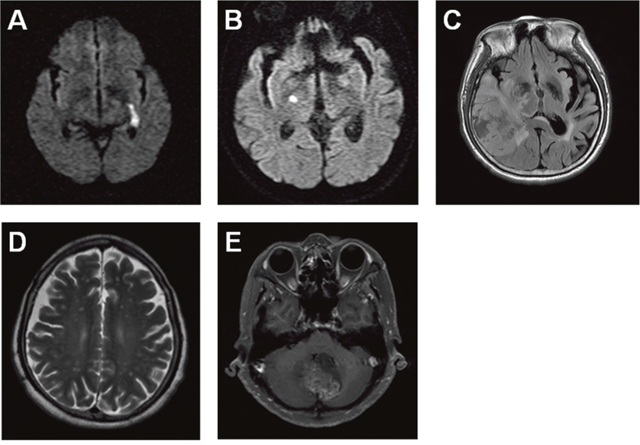

We retrospectively reviewed malignant glioma cases using brain MRI images and the past histories diagnosed in the Chi Mei Foundation Medical Center. There were 21 GBMs (WHO grade IV), 8 anaplastic astrocytomas (WHO grade III), 1 grade II astrocytoma, and 3 grade I astrocytomas. Two patients (6%) with ischemic stroke before the malignant glioma were diagnosed and belonged to the group of 21 GBMs. One case is a 72 year-old male with first left internal capsule acute infarction on January 21, 2007 and second right hypothalamus acute infarction on April 2, 2009 (Figure 1A and 1B). The patient received clinical follow up but right temporal GBM was diagnosed on June 21, 2016 (Figure 1C). Another case is a 67 year-old female with history of ischemic stroke about 5 years ago and cerebellar vermis GBM was diagnosed on May 21, 2015 with the image revealing cerebellar GBM with bilateral frontoparietal subcortical old infarction (Figure 1D and 1E). These results reveal a higher possibility of stroke in relation with developing malignant glioma.

Figure 1: Two GBM cases are diagnosed previously with ischemic stroke using brain MRI images. The brain MRI images indicate a 72 year-old male patient with the left internal capsule acute infarction on January 21, 2007 (A) and the right hypothalamus acute infarction on April 2, 2009 (B), as well as the right temporal GBM on June 21, 2016 (C). The brain MRI images reveal a 67 year-old female patient with the bilateral frontoparietal subcortical old infarction (D) and the cerebellar vermis GBM on May 21, 2015 (E).